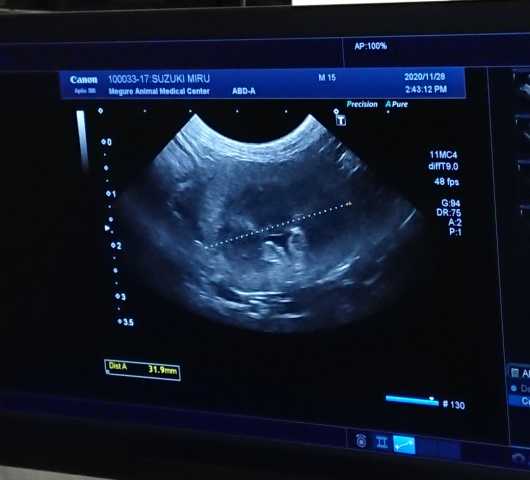

​​ 本日は、ミル、キコ、ヒメが定期通院で状態チェック

毎回、病院に行く途中でオシッコを漏らしてしまい尿検査が出来ていなかったミル。

本日は、お漏らしせずに、病院で採尿が出来ました。

腎臓も年齢の割には状態も良く、問題無し